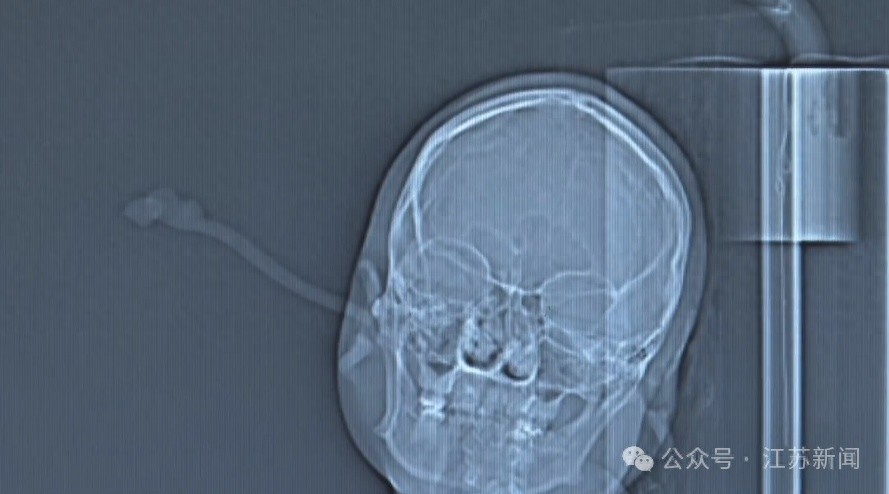

近日,江苏别称女子因“偷懒”睡前未取下金属发簪在夜间翻身时失慎将发簪从右耳插入直抵后脑勺经病院查验所幸发簪插入力度不大仅停留在骨质名义未伤及骨骼深层与颅内在明确伤情后医师赶紧实行了手术将发簪告捷取出 此类不测并非个例小坊此前就曾报说念过多起访佛事件↓↓↓旧年十月四川的胡先生和女友骑电动车时失慎摔跤由于女友头上戴了鲨鱼夹且脑着地受力导致头骨骨折成了植物东说念主 2023年12月浙江义乌别称女子发生车祸时鲨鱼夹奏凯插进后脑头皮而且还终点深 2023年10月27日安徽淮北一13岁女孩戴鲨鱼夹脚滑跌倒夹